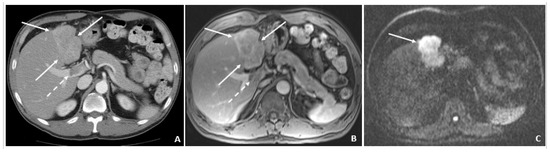

A 58-year-old male was found to have CHB on a routine examination in May 2007. HBV DNA was 4.6 × 105 copies/mL. He was started on telbivudine. The AFP was 3.2 ng/mL in May 2008 with AFP-L3% of 13.8. The MRI in July 2008 showed cirrhosis and no tumor. In August 2008, the AFP remained low at 3.2 ng/mL, but there was a rise in the AFP-L3% to 33.6. The AFP-L3% continued to rise to 69.7 by November 2008, while the absolute AFP value remained at 7.9 ng/mL. In March 2009, the AFP rose to 24.1 ng/mL, and the AFP-L3% at this time was continuing to rise to 87.7. At this time, the abdominal MRI showed a 2.4 × 2.0 cm HCC. He underwent cryoablation followed by radiofrequency tumor ablation and TACE (March and August 2009). These values are outlined in Table 5.

Figure 5.

Triphasic CT at the time of HCC diagnosis (March 2009). (A) The precontrast image shows a hypodense lesion (arrow) at the site of the punctate hyperenhancing lesion shown in Figure 4. (B) The corresponding arterial-phase postcontrast image reveals hyperenhancement (arrow). (C) The portal-phase postcontrast image shows washout (arrow), and all features are typical of HCC and confirm the diagnosis in the setting of chronic HBV.